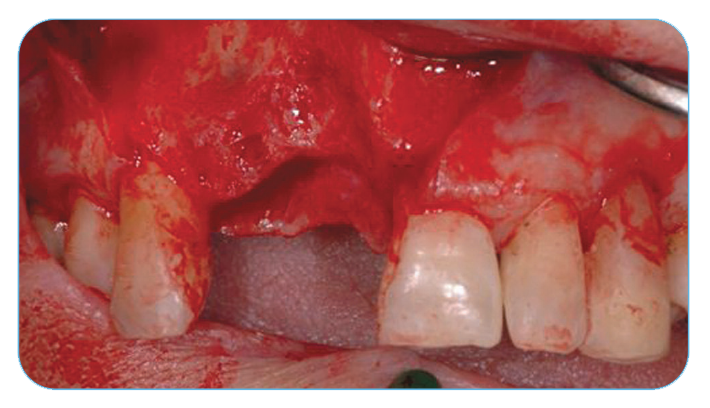

Anterior Ridge Augmentation

Fig. 1. Extraction sockets of the four maxillary incisors and immediate implant placement.